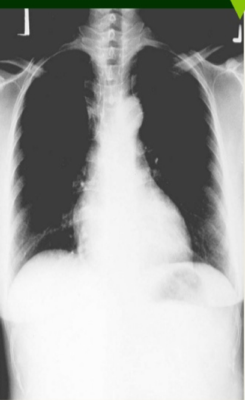

Paciente de sexo femenino, de 30 años aproximadamente, acusa antecedentes de obesidad tabaquismo sumado a una hipertensión arterial. Se presenta radiografía de corazón. ¿Cuál es su diagnóstico?

Answer

• Un aumento del tamaño de la silueta cardíaca a expensas del ventrículo derecho y contracción aórtica.

• Cardiopatía Hipertensiva sumado a un aumento del tamaño de la silueta cardíaca a expensas del ventrículo izquierdo y elongación aórtica.

• Miocardiopatía restrictiva caracterizada porque el corazón se vuelve muy rígido y tiene dificultades para llenarse.

• Miocardiopatía restrictiva. caracterizada porque el corazón se vuelve muy flexible teniendo dificultades en el bombeo de sangre.